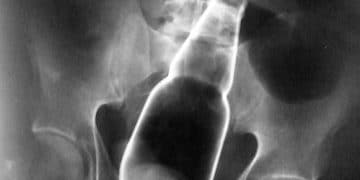

Yabancı Madde, bir maddenin kendisinden başka bulunan her maddeye denir. Foreign body